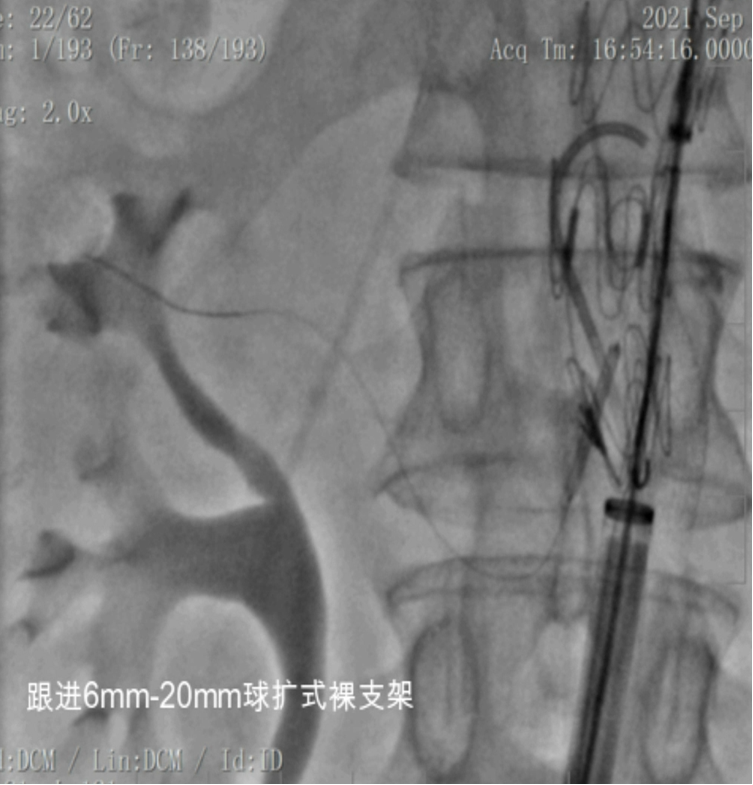

③ 桥接支架

球扩覆膜支架:更大的支撑强度,能够以更小的位移而精确部署

VBX:支撑力不足,柔顺性高,适型性好

裸支架:应用较少,非扩张区域

Express Vascular,支架扭结抗性相对较高

自膨覆膜+球扩裸支架

裸支架进一步提供支撑力,内衬,纠正扭曲

桥接血管内漏问题

开窗支架分支支架与主体支架是线与面的接触,可能导致内漏、脱载;

缝合内分支/外分支增加接触面积,减少内漏、增强系统的稳定性;

根据内脏区主动脉是否扩张、附近有无破口决定使用覆膜支架或裸支架;

充分重叠范围,分支动脉支架进入主动脉支架>1 cm。